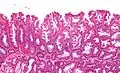

SSLs are diagnosed by their microscopic appearance; histomorphologically, they are characterized by (1) basal dilation of the crypts, (2) basal crypt serration, (3) crypts that run horizontal to the basement membrane (horizontal crypts), and (4) crypt branching. The most common of these features is basal dilation of the crypts.

Unlike conventional colonic adenomas (e.g. tubular adenoma, villous adenoma), they do not (typically) have nuclear changes (nuclear hyperchromatism, nuclear crowding, elliptical/cigar-shaped nuclei).

Intermediate magnification micrograph of an SSL.